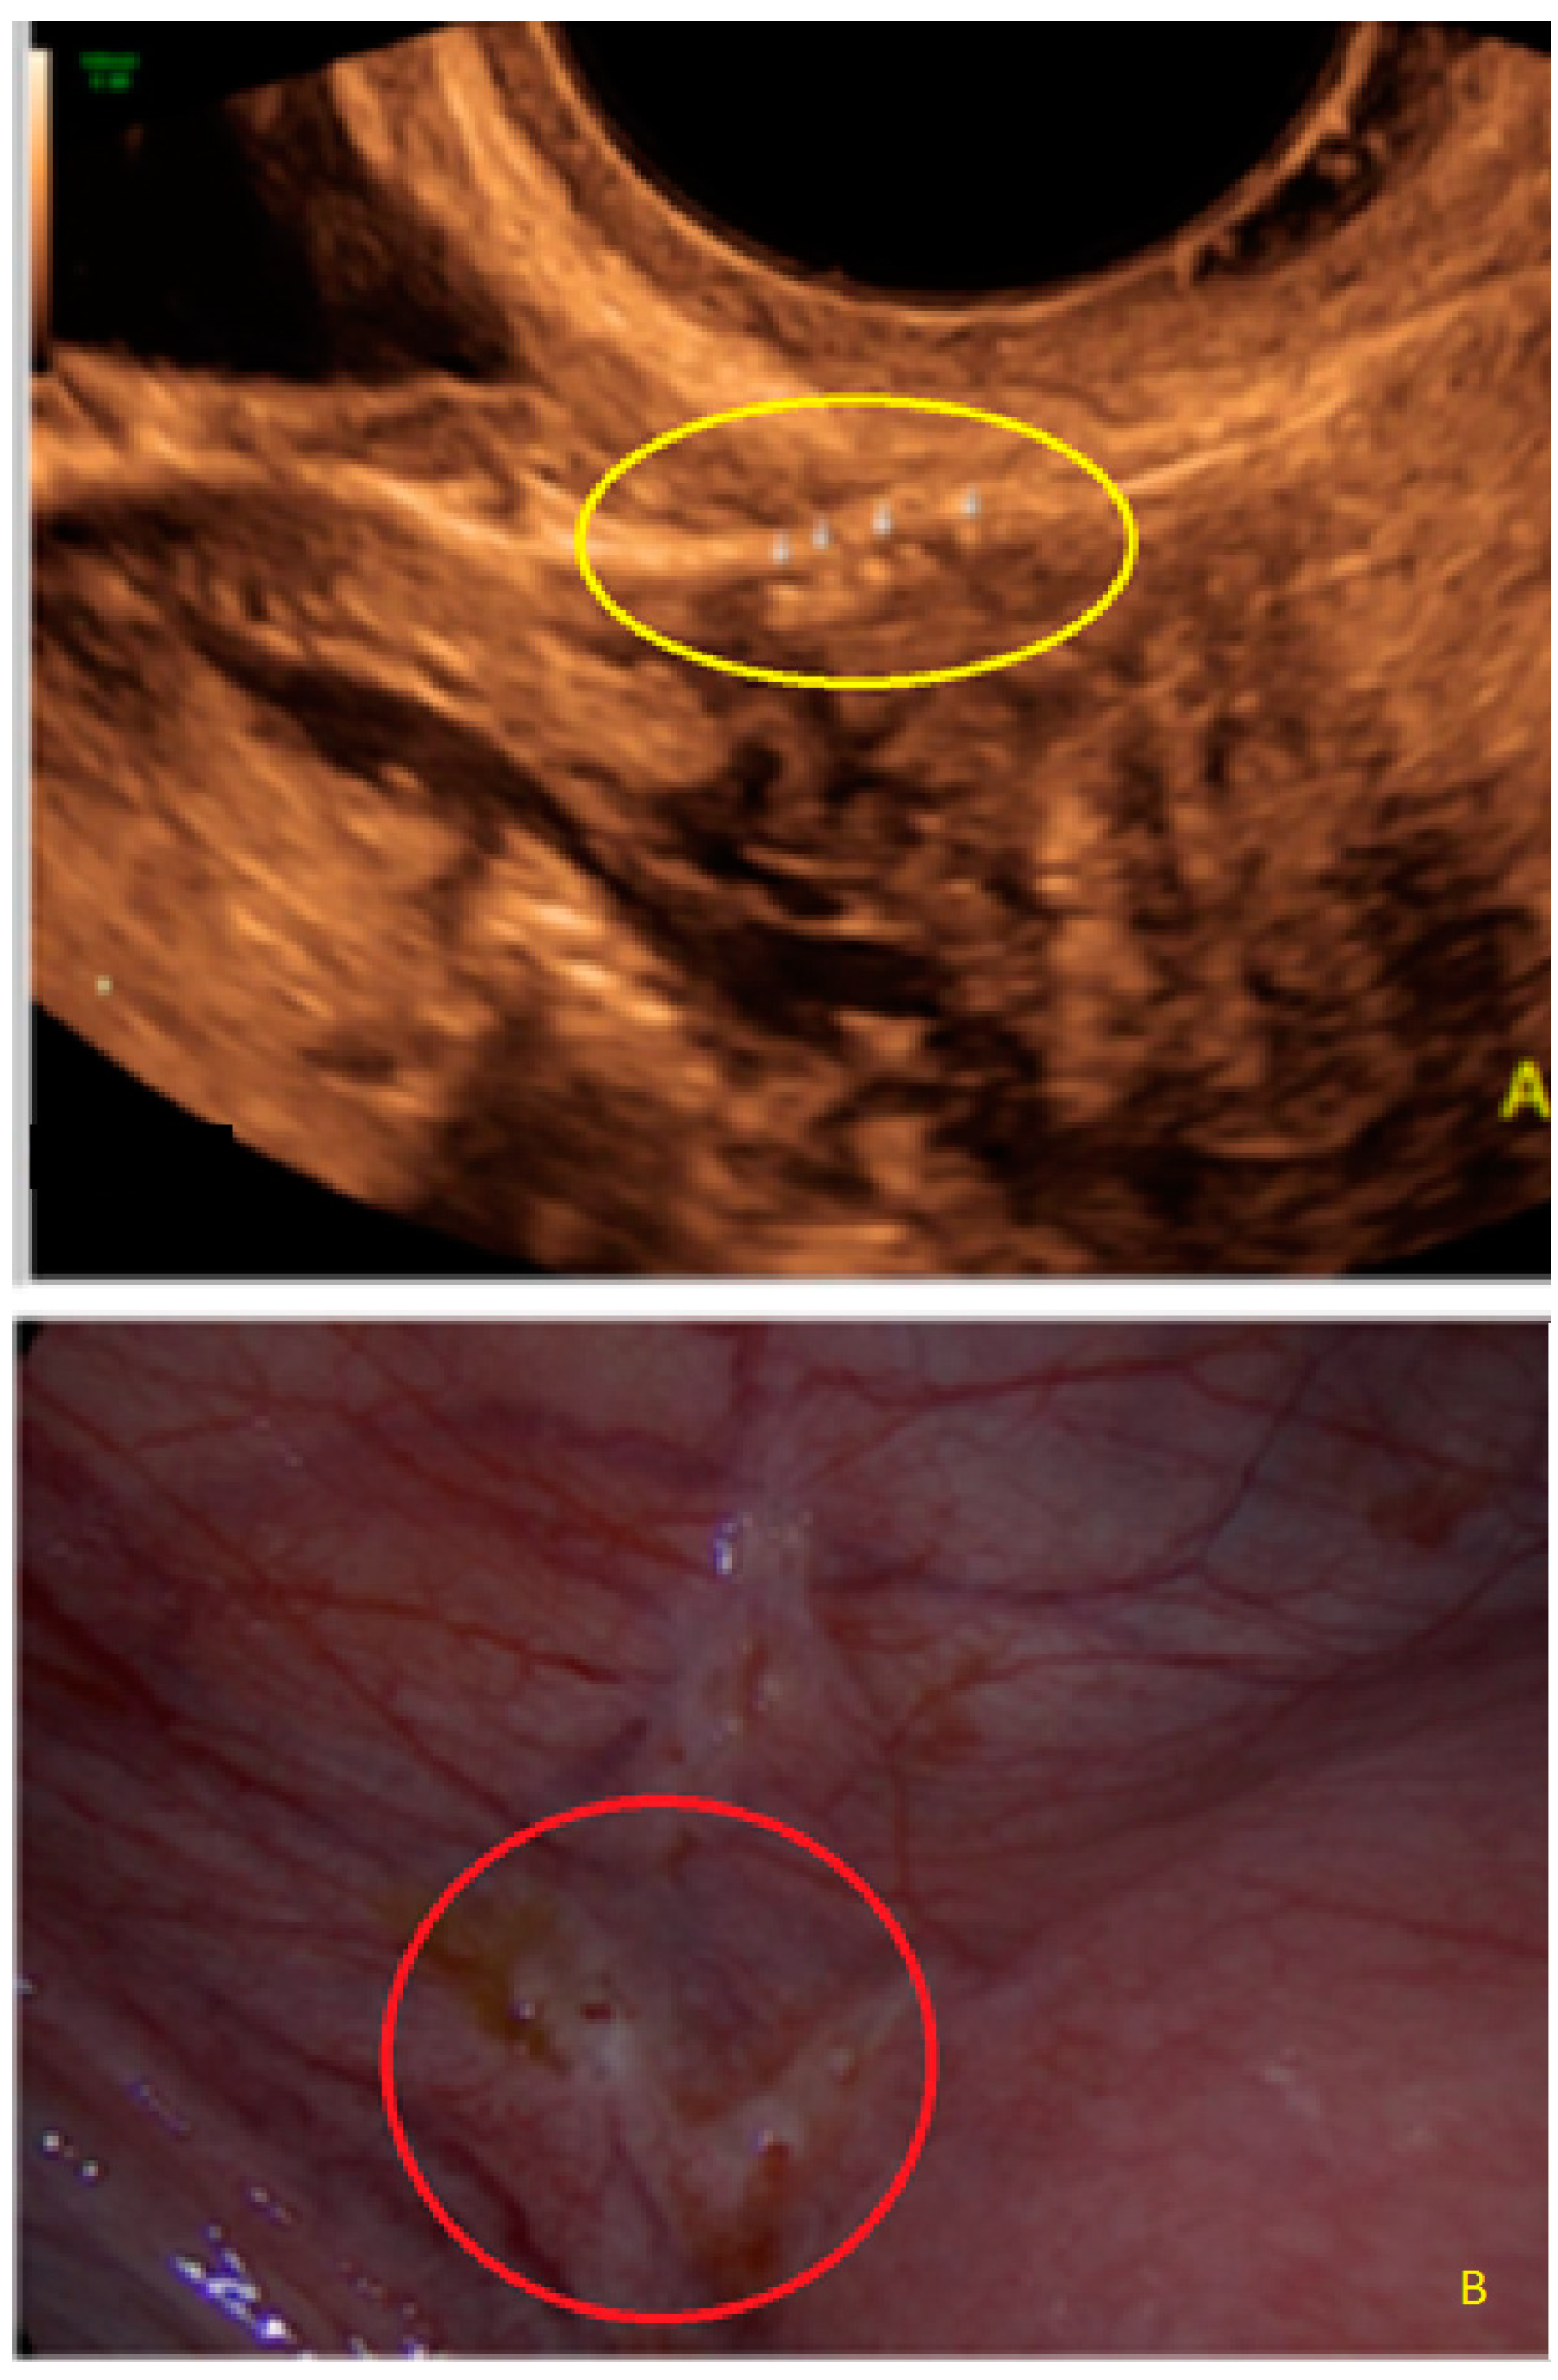

- The presence of hypoechogenic associated tissue (hypoechoic areas surrounding a small cyst area; we called this a “hat”). This tissue does not protrude or invaginate the peritoneal surface.

- The presence of hyperechoic foci (we called this a “pearl”).